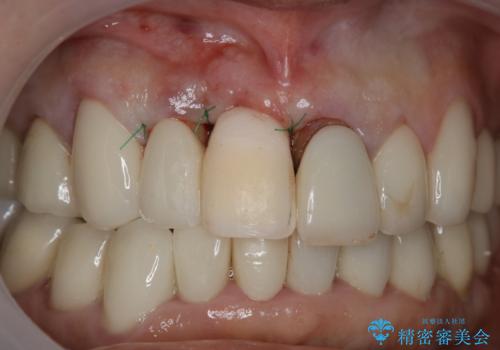

患者様のご要望もあり、審美性の確保ができる抜歯早期埋入→埋入後即時荷重という手術法を取りました。

近年、インプラントの素材や手術法の研究が進み、保存不可能となった歯牙に対して抜歯してすぐインプラントを埋入し、さらに直後から仮歯がを入れ噛むことができる【抜歯即時埋入】【即時荷重】という技法が確立されました。

それと比較すると、今回の方法では骨にしっかりと固定されているインプラントに単独で仮歯を装着することができるためフロスも通せますし、ある程度負荷のかかる食事も気にせずできるようになります。